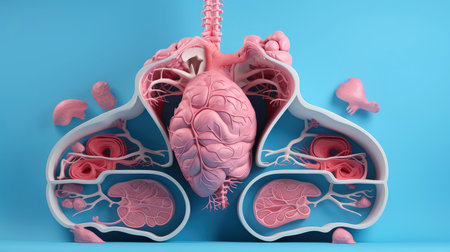

3D illustration of the human organ systems, Human internal organs. Anatomy. Nervous, circulatory, digestive, excretory, urinary,and bone systems. Medical education concept, Generative AI illustration

3D illustration of the human organ systems, Human internal organs. Anatomy. Nervous, circulatory, digestive, excretory, urinary,and bone systems. Medical education concept, Generative AI illustration

3D illustration of the human organ systems, Human internal organs. Anatomy. Nervous, circulatory, digestive, excretory, urinary,and bone systems. Medical education concept, Generative AI illustration

3D illustration of the human organ systems, Human internal organs. Anatomy. Nervous, circulatory, digestive, excretory, urinary,and bone systems. Medical education concept, Generative AI illustration

3D illustration of the human organ systems, Human internal organs. Anatomy. Nervous, circulatory, digestive, excretory, urinary,and bone systems. Medical education concept, Generative AI illustration

3D illustration of the human organ systems, Human internal organs. Anatomy. Nervous, circulatory, digestive, excretory, urinary,and bone systems. Medical education concept, Generative AI illustration